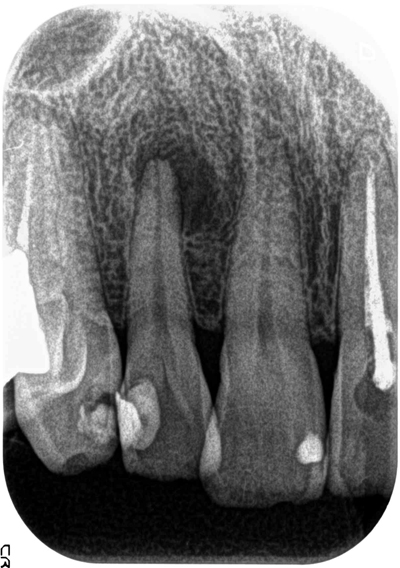

2Dのレントゲンではわずかな病巣としか見えませんが、3DのCTでは内部にかなり大きな病変が在るのが良くわかります。

治療前

治療後